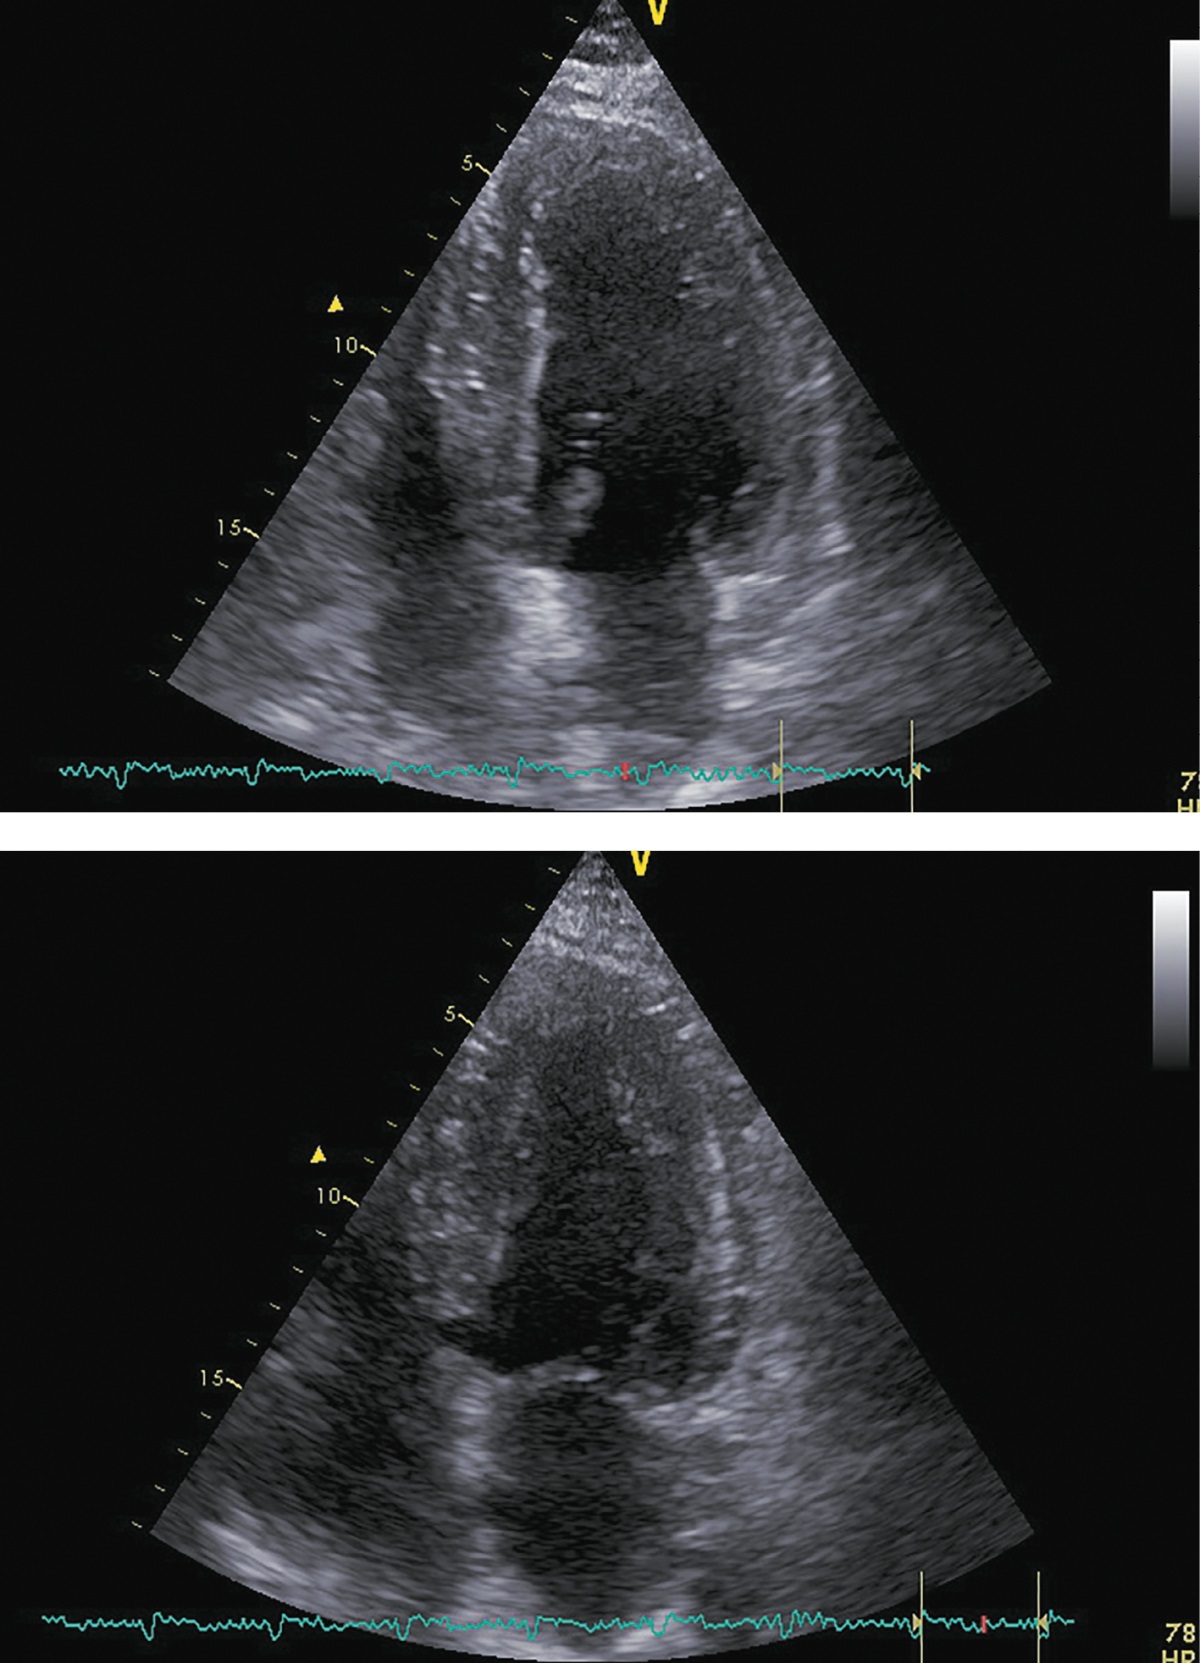

В ноябре 2017 г. пациент госпитализирован повторно для проведения нейрохирургического лечения. Пациент указал, что принимал предписанную терапию в полном объеме. Каких-либо нежелательных лекарственных реакций не выявлено. На фоне лечения симптомы ХСН заметно регрессировали, толерантность к физическим нагрузкам возросла до уровня II ф.к. по NYHA. Физикальной симптоматики легочного застоя и увеличения печени не отмечалось. При контрольной ЭХОКГ (рис. 5; табл. 3) выявлены уменьшение размеров и объемов левого желудочка, значительное увеличение ФВ ЛЖ (до 43%) и снижение класса диастолической дисфункции ЛЖ.

Рисунок 5. ЭХОКГ перед аденомэктомией.

Примечание: верхушечная 4-камерная позиция (сверху представлен кадр в диастолу, снизу — в систолу).

Таблица 3. ЭХОКГ-показатели перед аденомэктомией

|

Показатель |

Значение/индекс |

Объем левого предсердия |

100 мл/54 мл/м² |

Передне-задний размер левого желудочка |

7,20 см/2,89 см/м² |

Конечно-диастолический объем левого желудочка |

285 мл/117 мл/м² |

Конечно-систолический объем левого желудочка |

162 мл/67 мл/м² |

Локальная кинетика левого желудочка |

умеренный диффузный гипокинез |

Фракция выброса левого желудочка (усреднение по 4- и 2-камерным верхушечным позициям) |

43% |

Диастолическая функция левого желудочка |

градация II, псевдо-нормальный тип |

Конечно-диастолическая площадь правого желудочка |

25,0 см²/10,0 см²/м² |

Конечно-систолическая площадь правого желудочка |

12,0 см²/4,8 см/м² |

Фракция систолического уменьшения площади |

52% |

Расчетное систолическое давление в легочной артерии |

43 мм рт.ст. |